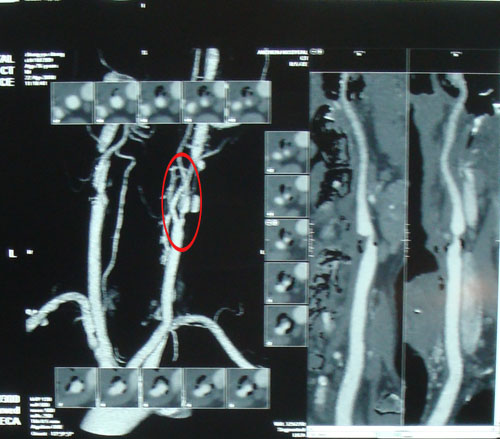

DSA:全身动脉多发粥样硬化,左侧髂内动脉闭塞,右侧颈内动脉起始部狭窄约50%,左侧颈内动脉起始部狭窄约90%。

本例患者左侧颈内动脉严重狭窄达90%,但其症状仅表现为反复发作性头晕,未出现严重的中风发作,因此为预防中风发作,应行CEA取出斑块,彻底去除病变。 2009年6月25日,协作组张勤奕教授在北京大学人民医院为其成功实施了左侧颈内动脉内膜剥脱术。术后患者恢复很好。